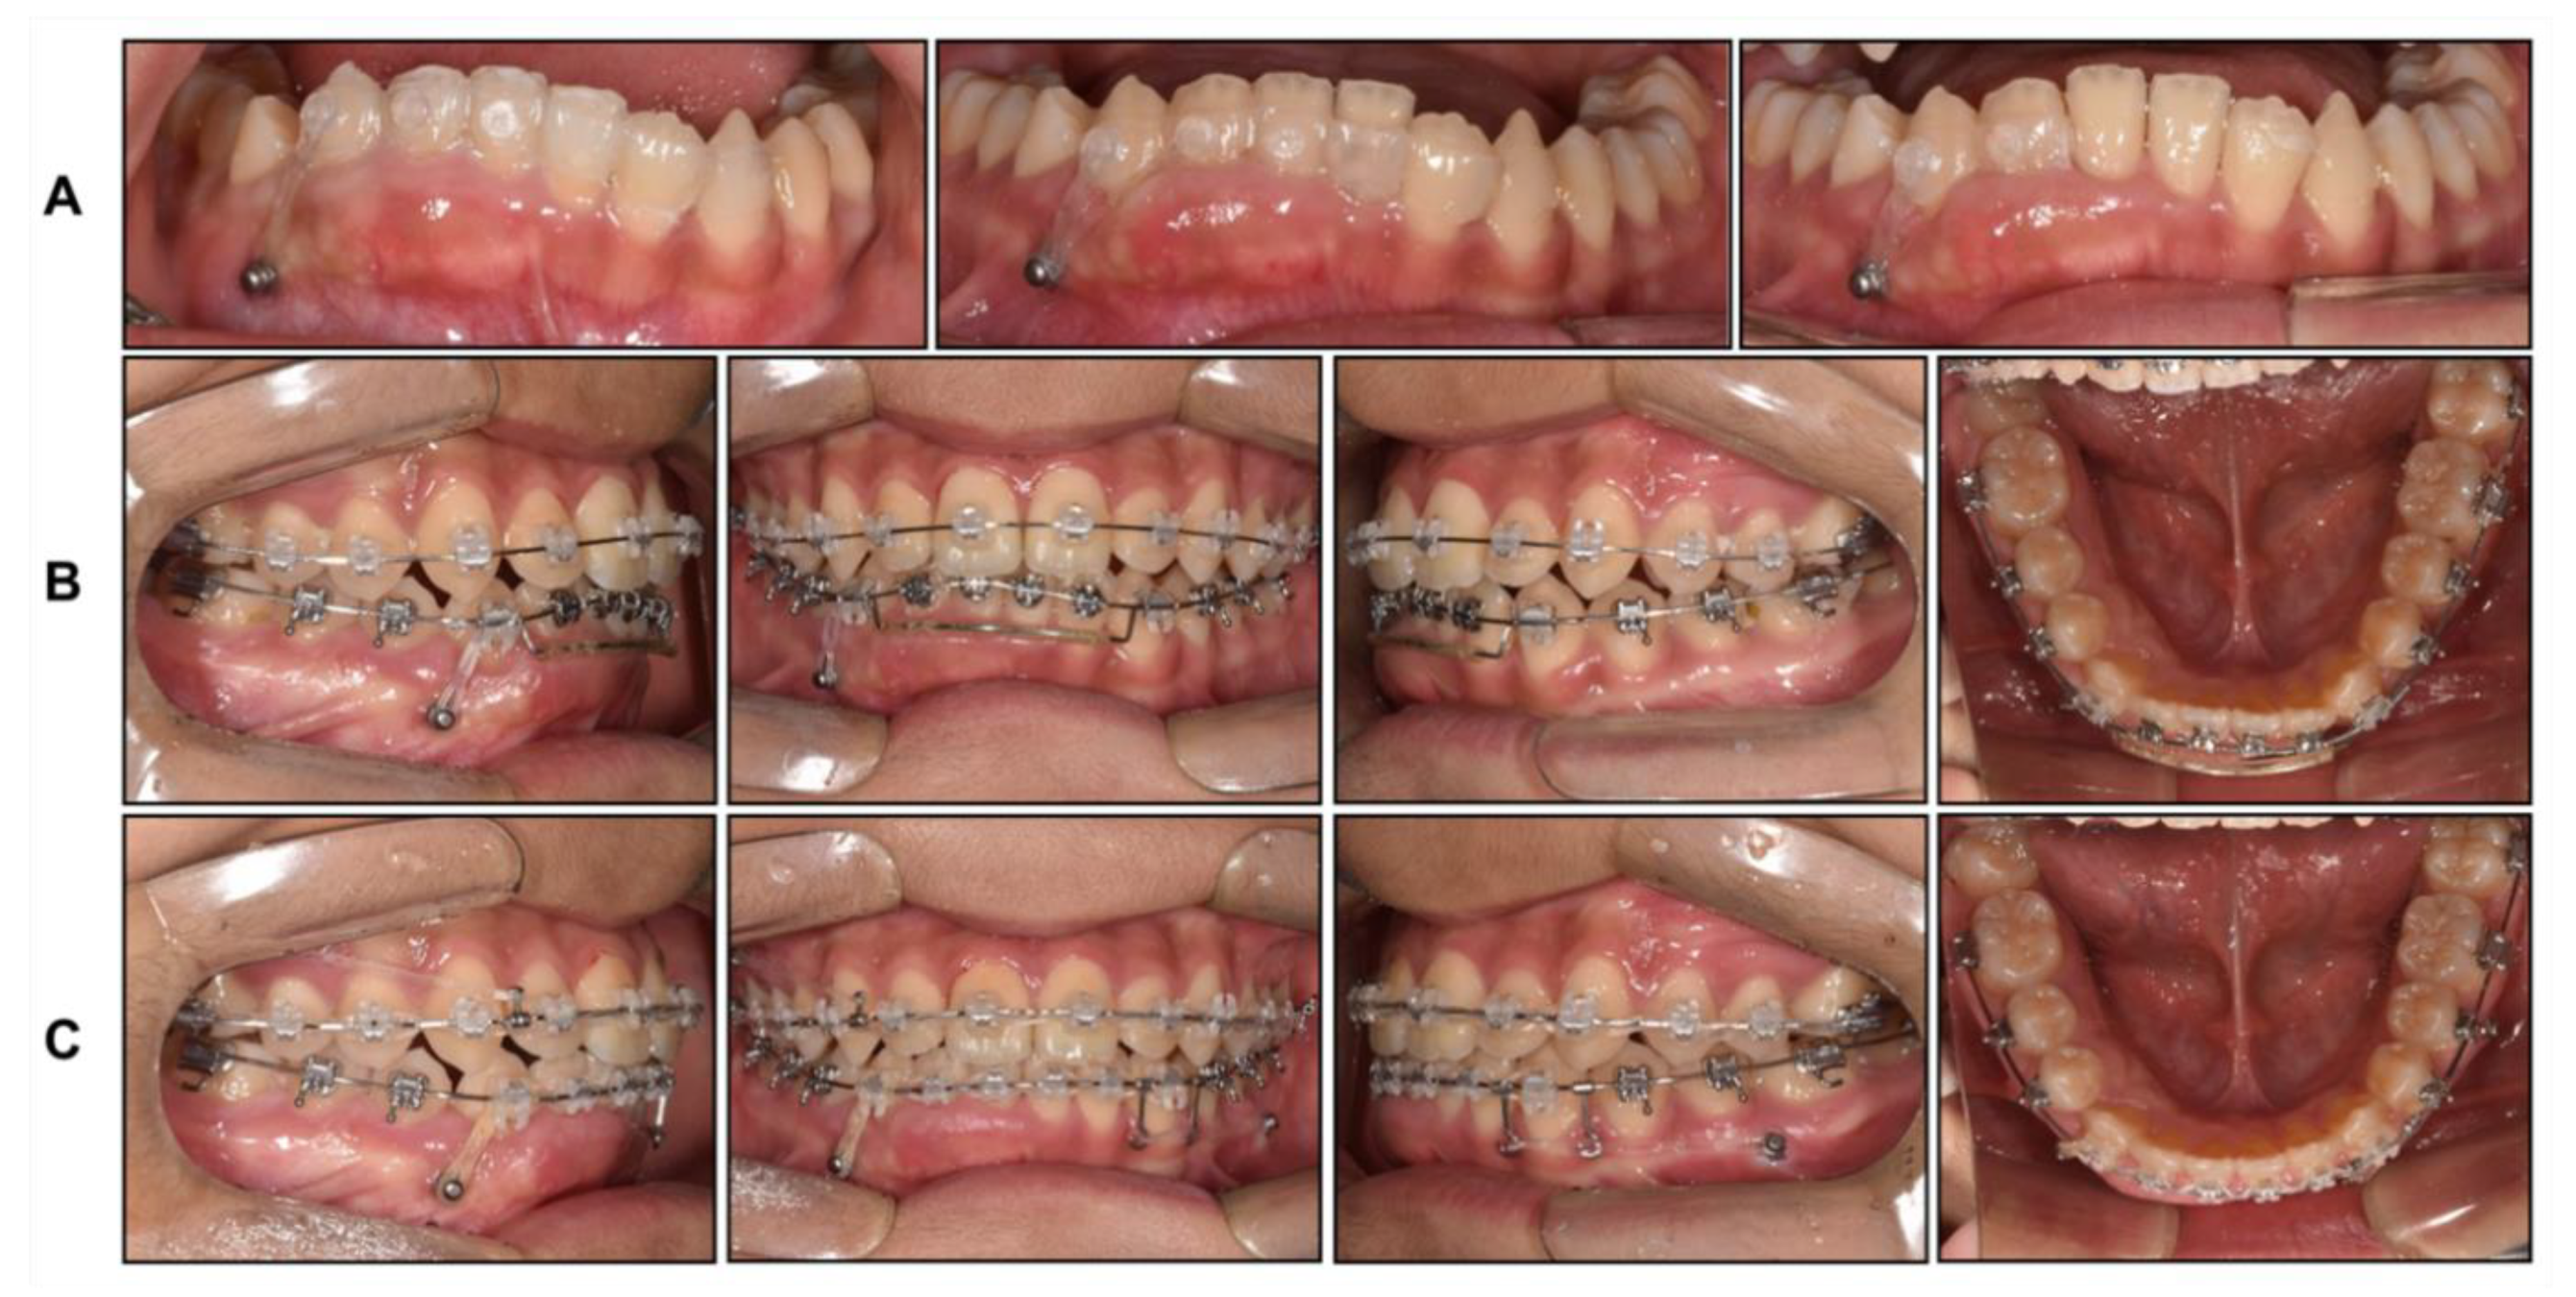

The patient was at stage 4 of the cervical vertebral maturation index in the deceleration phase of growth, and we decided to start phase 2 treatment. First, we decided to correct the canting of the mandibular anterior teeth by the intrusion of the right side with the segmental technique to avoid side effects. Due to the deep bite, it was not easy to place fixed braces on the mandibular anterior teeth. Therefore, we placed a fixed clear attachment with multiple clear buttons to splint the six anterior teeth of the mandible and started to intrusively rotate the anterior teeth with a mini screw, which was inserted between the mandibular right canine and the first premolar (Figure 9A).

After 4 months, the canting of the mandibular anterior teeth was much improved, and we placed fixed braces for comprehensive orthodontic treatment. We maintained the mild intrusive force on the mandibular right canine with an elastic chain during the leveling and alignment procedures to prevent relapse (Figure 9B), following which dental midline correction was performed with mini screws inserted between the first molar and second premolar of the right maxilla and left mandible (Figure 9C).

Figure 9. Intraoral photographs during phase 2 treatment: (A) Progressive intrusion of mandibular right anterior teeth using fixed clear attachment; (B) Leveling and alignment; (C) Midline correction using mini screws.